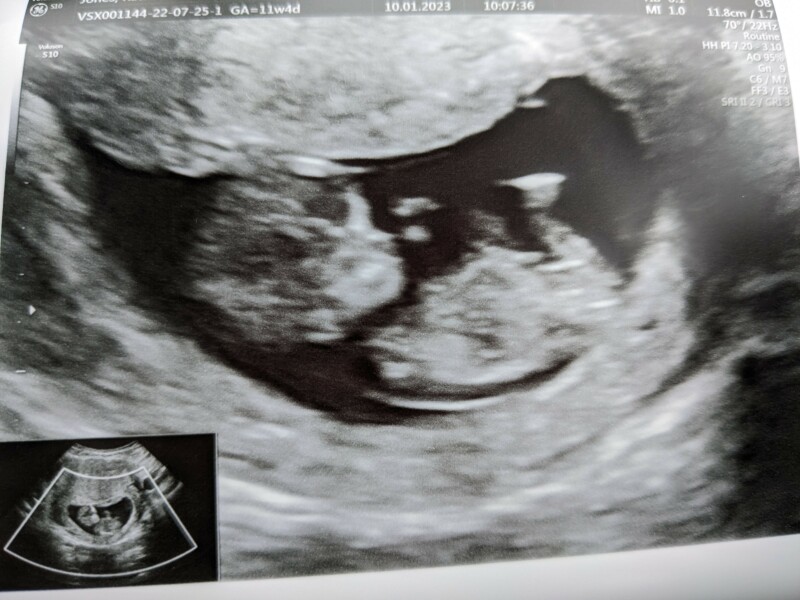

Phew! One happy healthy baby. Heartbeat around 150-160bpm. Sonographer said it looks like a perfect baby. Feel relieved now!

Anyone else due July after a MC? 🌈

allgoodthings84 · 10/01/2023 11:05

@rach971 that’s fantastic news! A lovely scan photo

@rach971 amazing news and beautiful picture. So happy for you. Sending big hugs your way. Really praying this will be me in two weeks time. Just popped to mcds for a little treat so hoping that’s a sign as really fancied a cheeseburger and hot choc.